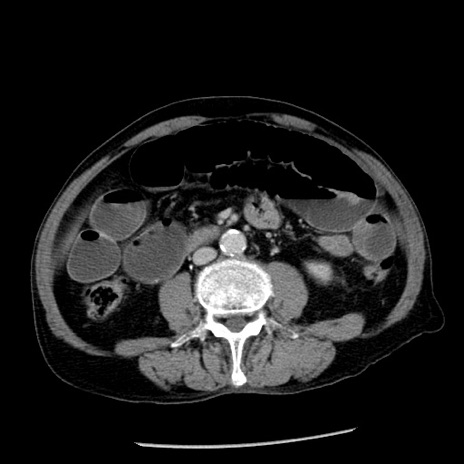

冠状断像

症例26(横断像)

【症例】80歳代男性

【主訴】嘔吐

【現病歴】昨晩2回嘔吐あり、今朝になっても嘔吐あり。来院。

【既往歴】胃潰瘍

【身体所見】意識清明、BT 37.6℃、BP 166/95mmHg、HR 100bpm、SpO2 97%、腹部:平坦・軟、腸蠕動音聴取良好、圧痛なし。

【データ】WBC 21900、CRP 1.46